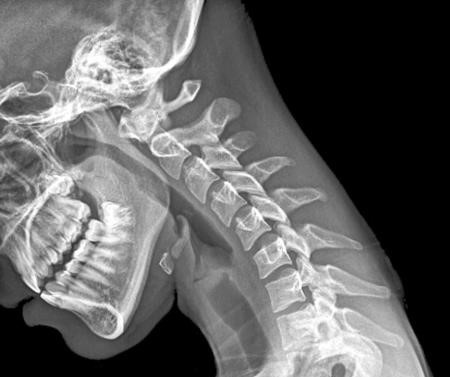

Sau khi chụp X-quang cho cô bé đến từ thành phố Thanh Đảo (tỉnh Sơn Đông, Trung Quốc), các bác sĩ kết luận xương sống cổ của em đã bị biến dạng nên không thể ngẩng cao đầu, theo China News Service.

Đây là căn bệnh thường thấy ở những người trên 50 tuổi khi xương khớp bắt đầu thoái hóa, khiến bệnh nhân hay bị đau nhức và chóng mặt.

| Việc dùng điện thoại quá nhiều khiến một bé gái bị hỏng cổ vĩnh viễn. |